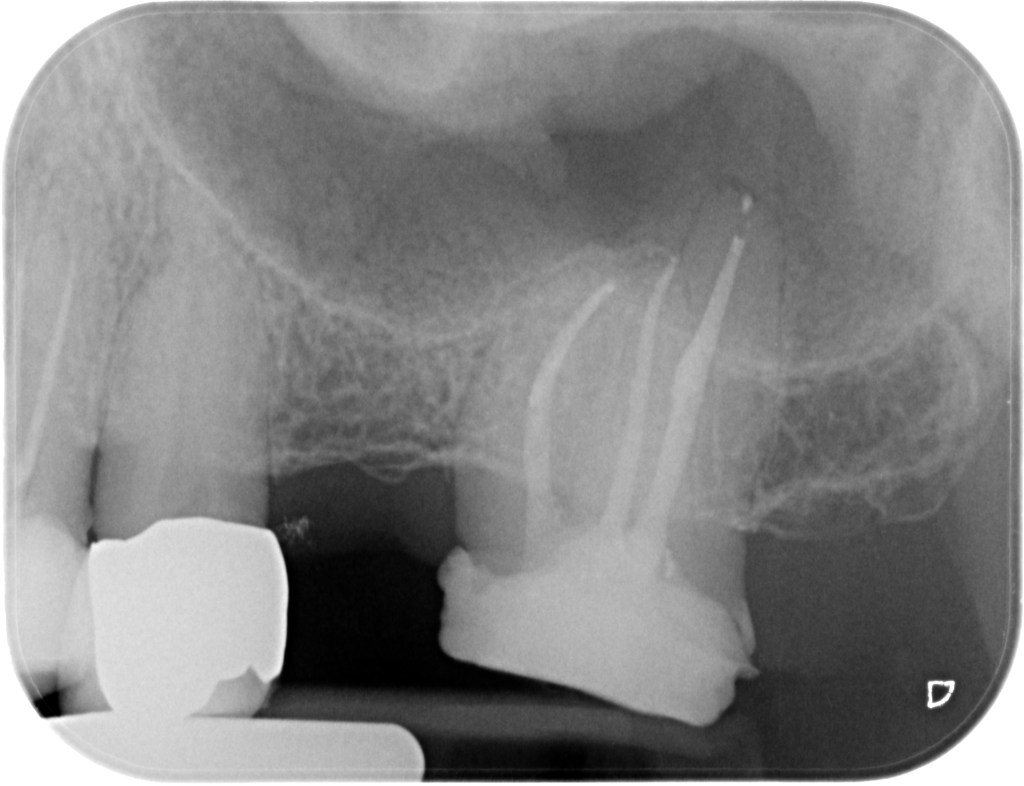

21.09.2021 Patient TG, geb. am 30.03.1974, Zahn 27, WF- Kontrolle